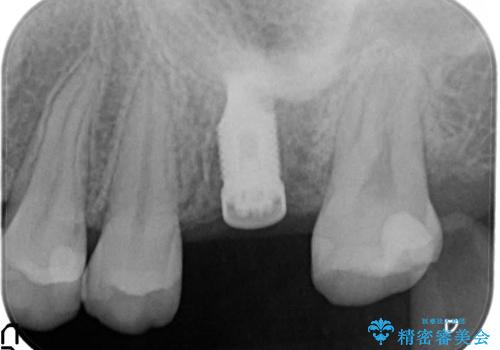

- 歯根破折を生じた奥歯を抜歯後、治癒の期間を経てインプラントを埋入

→2時手術の後、インプラントレベルの型どりにて上部構造まで完成させる

インプラントの種類:Zimmer spline